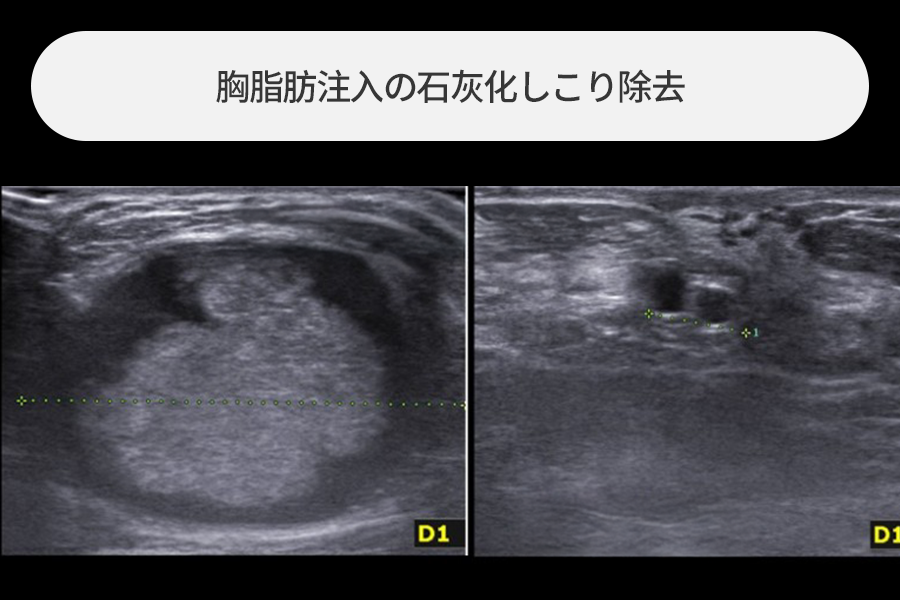

4~5cmの大きさの脂肪注入のしこり除去

胸への脂肪注入後に触れるしこりがあり来院された方で、

4~5cmサイズの大きな石灰化したしこりが観察されました。

サイズの大きい脂肪注入のしこりは急性炎症発生時の危険度が高いため、最大限早い除去が必要です。

超音波誘導下で正常組織を保存しながらしこりだけを安全に除去しました。